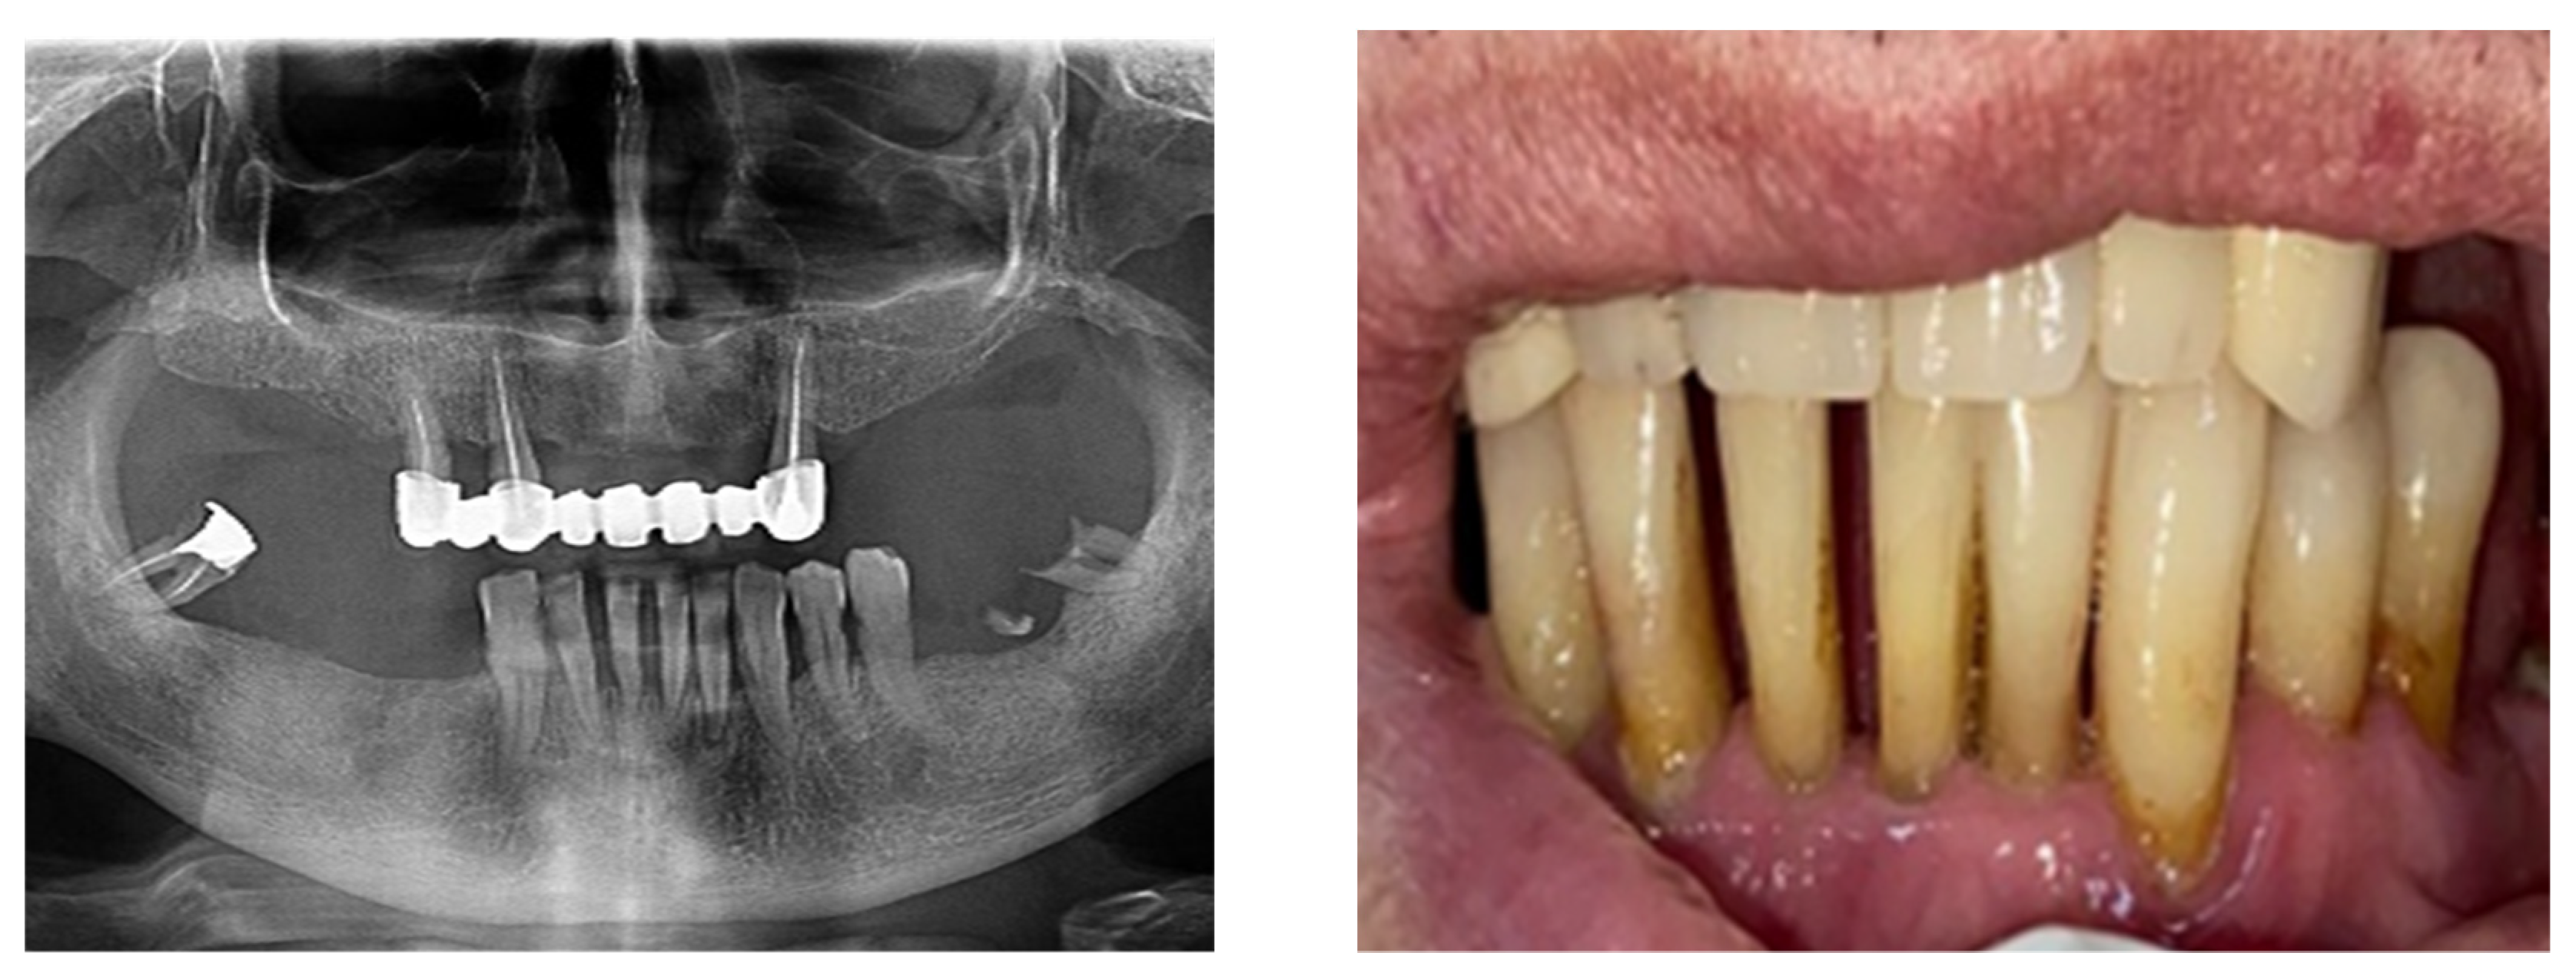

From www.researchgate.net

Effects of periodontitis associated tooth mobility with positive feedback Download Scientific Can Tooth Mobility Be Reversed Unlike plaque, bleeding on probing, and pocketing, this clinical measure rarely changes with scaling and root planing. This chapter describes the causes of tooth mobility and how it is related to occlusal trauma. Grade 2 is tooth mobility greater than 2. Yes, grade 1 tooth mobility can be reversed with scaling, root planning, and maintaining oral hygiene. In addition, prevention. Can Tooth Mobility Be Reversed.